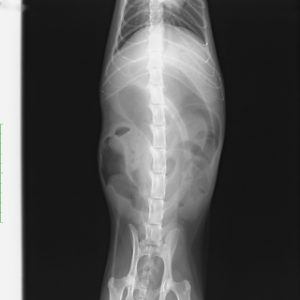

左が横向きの画像、右が仰向けの画像です。

レントゲン検査では、「小腸の拡張」「大小不同」が認められます。ソーセージ状にみえる黒い所は、小腸内に貯留した「ガス」です。

消化管は、言葉が示すように管(くだ)ですから、ある部分に多量にかつ腸管壁を押し広げるようにガスが溜まることは、不可能です。

絶対に、前後に移動してしますはずです。

ガスが貯留し、消化管が拡張しているということは消化管の運動機能低下や閉塞が疑われます。

腸には、小腸と大腸があることはご存知の方も多いと思います。

言葉どおり小腸は小さい(細い)腸です。しかし、レントゲンには大腸よりも大きく拡張した小腸が写っています。